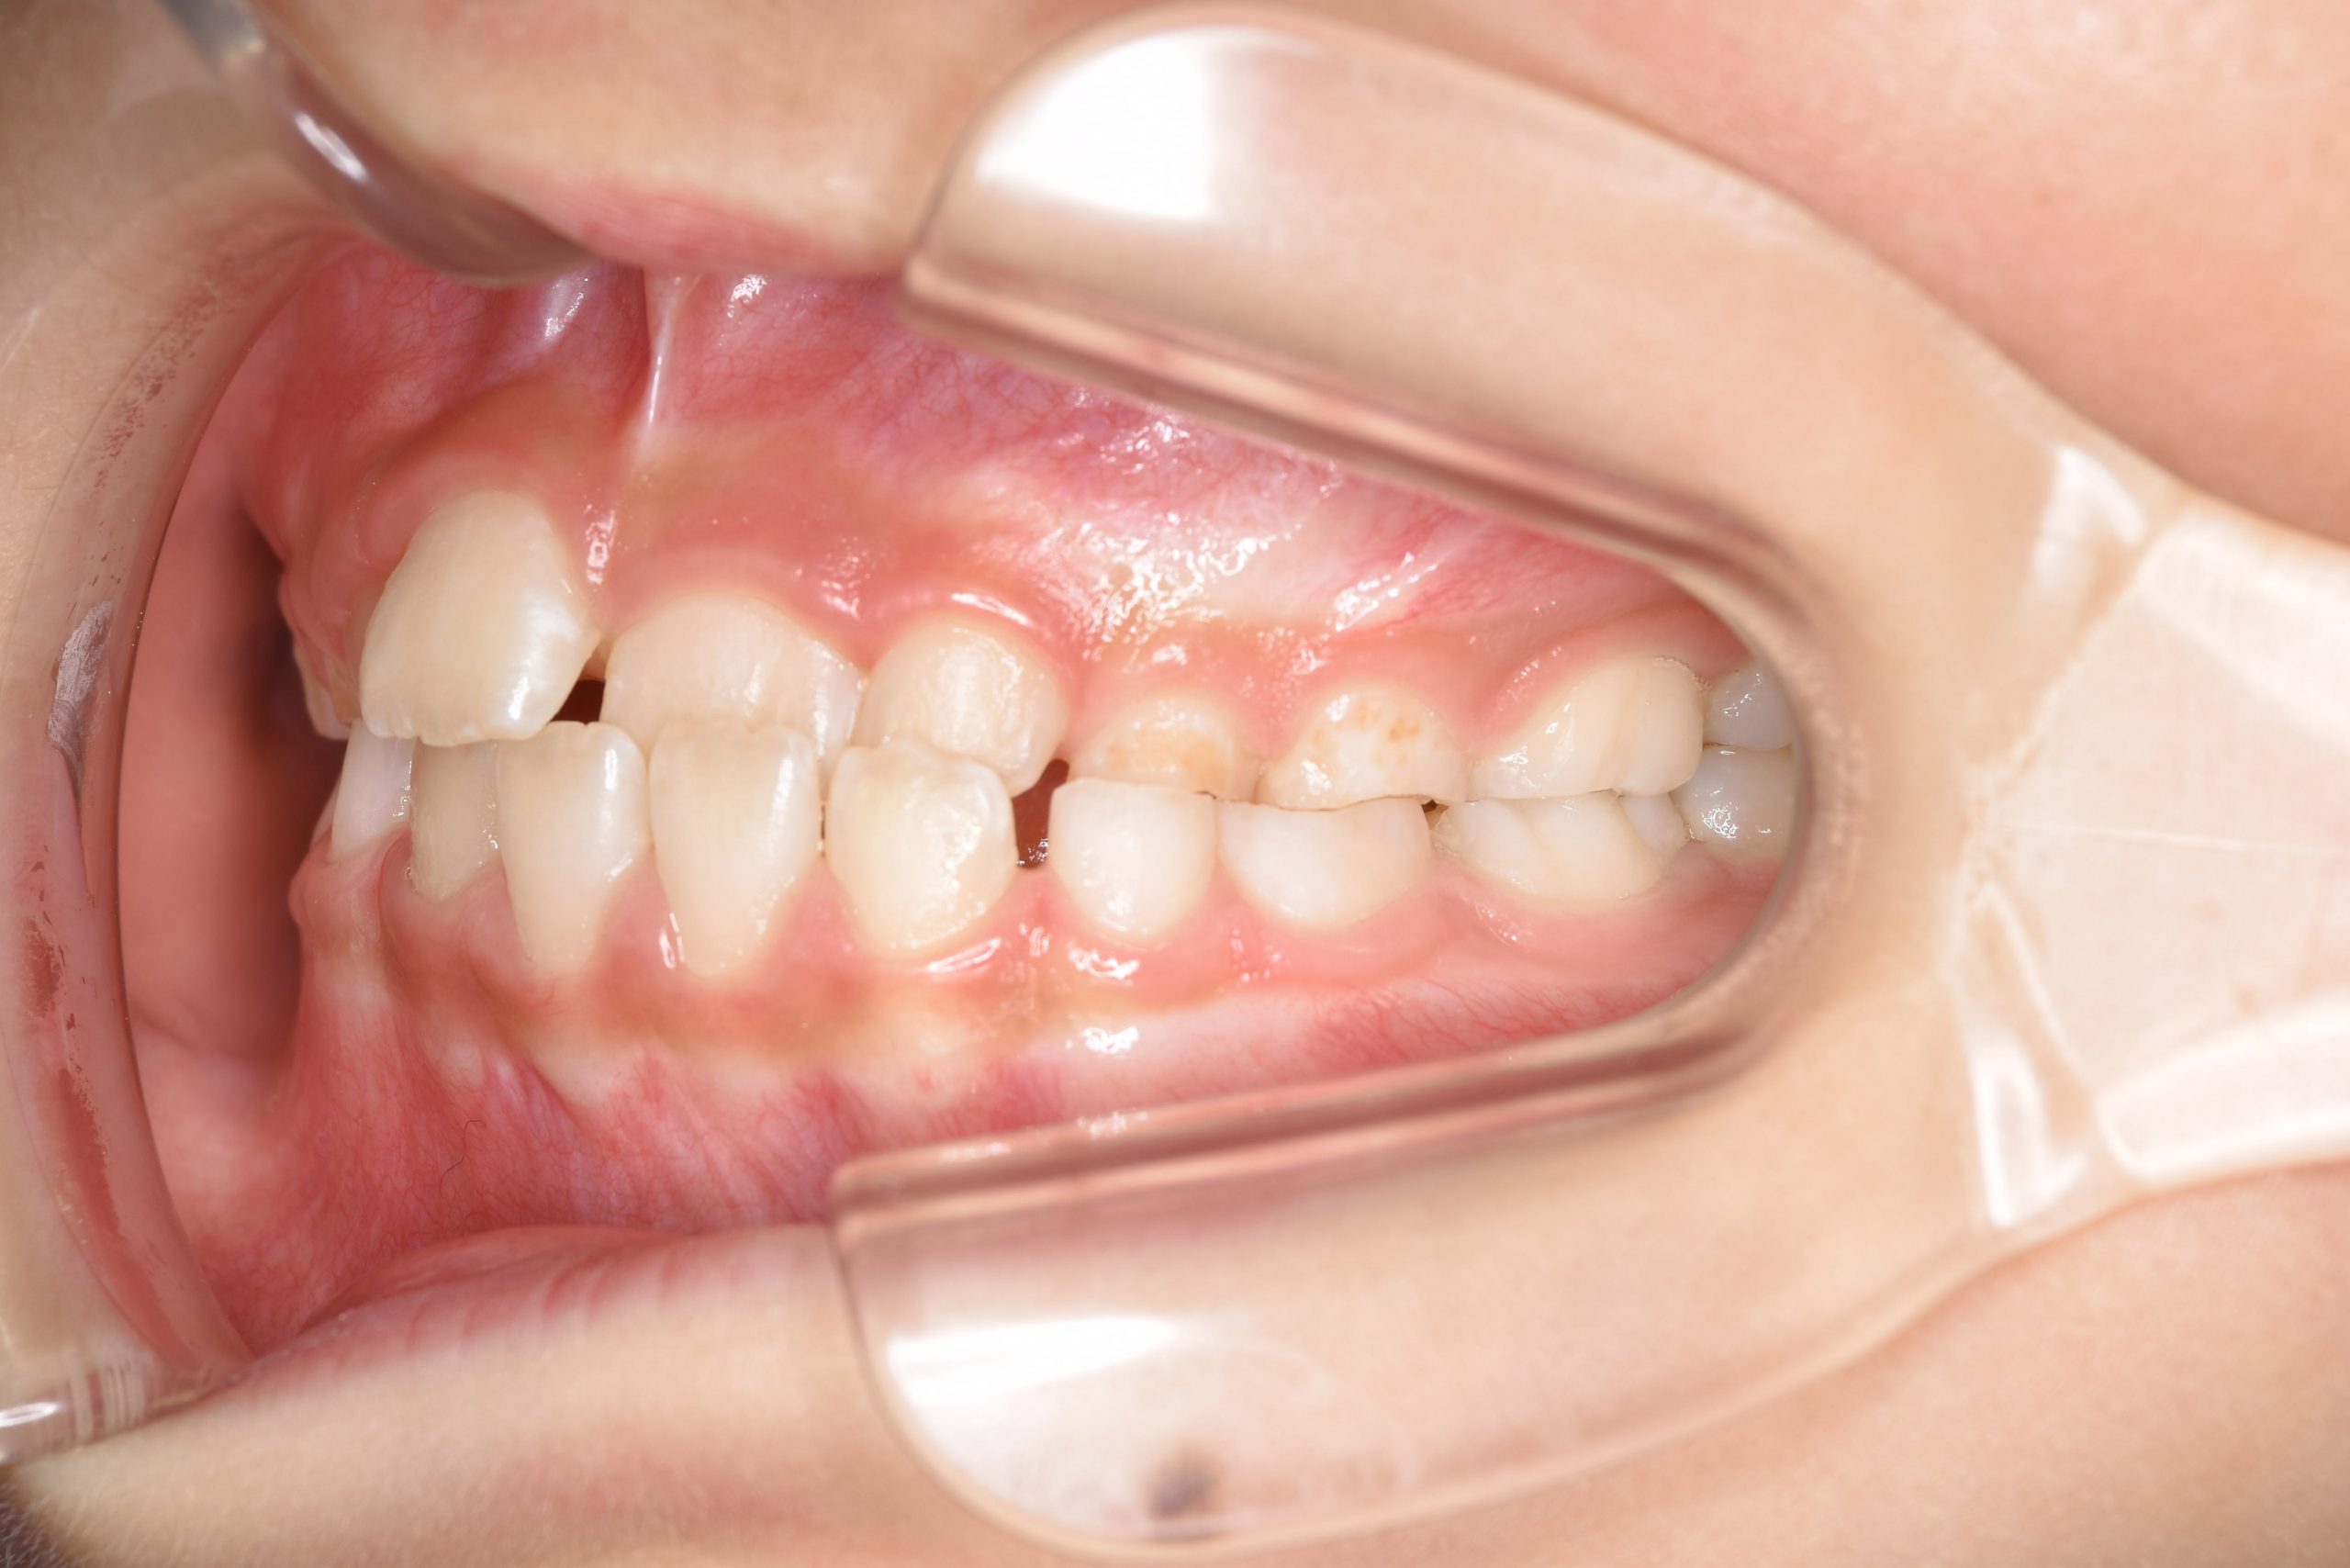

ビフォー

全顎ワイヤー矯正 症例_108

主訴 受け口|前歯がかみ合わない|顔貌

施術内容 小児矯正1期治療

治癒期間 3年11ヶ月間

費用 498,960円(税込)